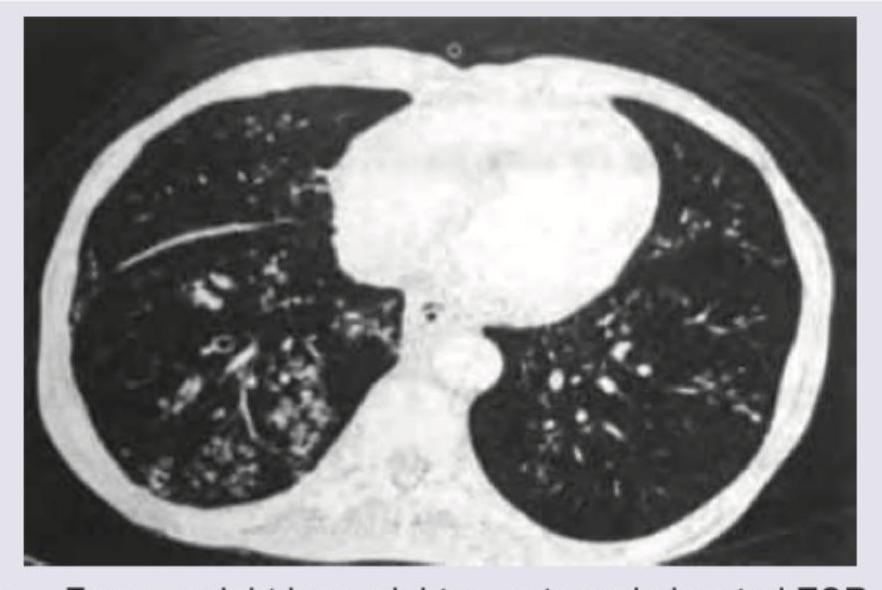

What is the most likely diagnosis in this 50-year-old woman?